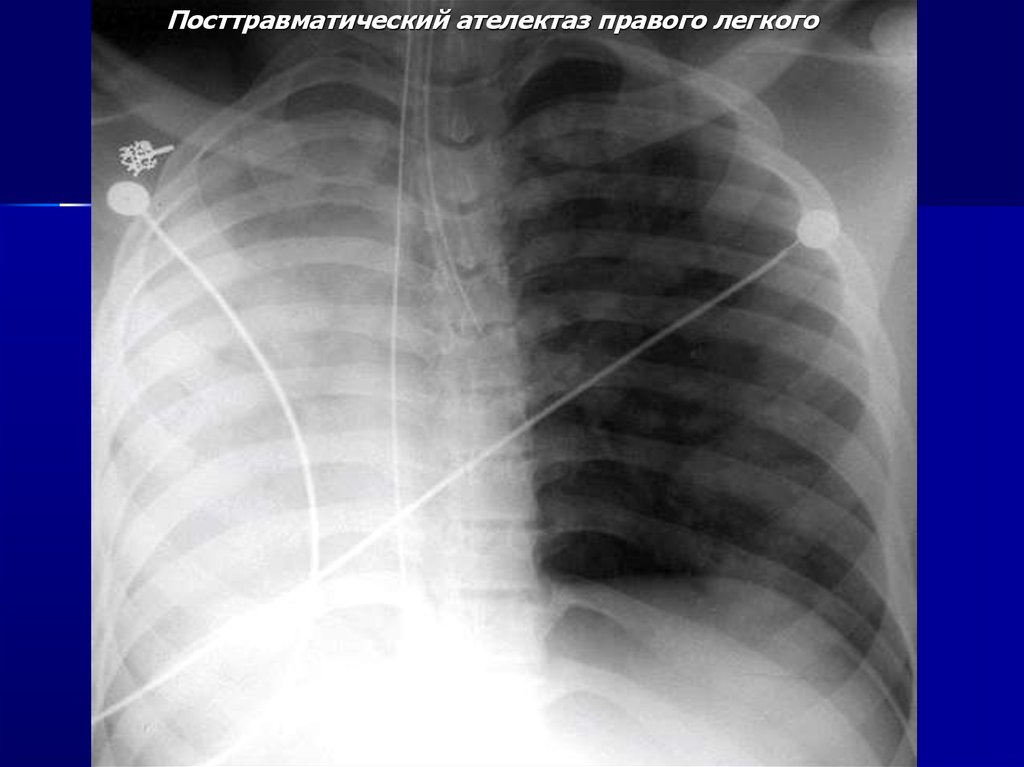

Посттравматический ателектаз правого легкого